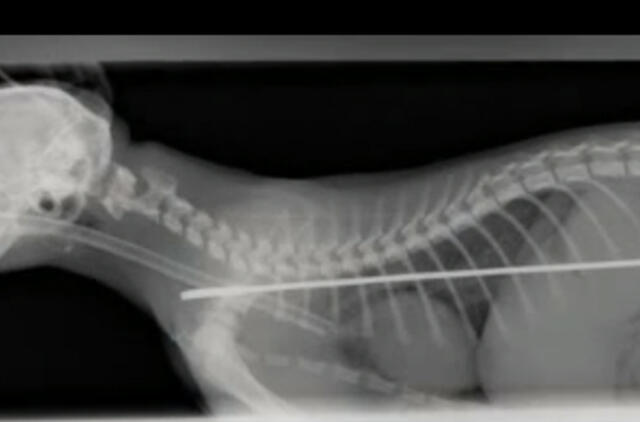

„Vieną naktį išgirdau garsų trenksmą ir užlipau į viršų pažiūrėti, kas atsitiko. Pamaniau, kad Alphie tiesiog nukrito nuo palangės. Jis atrodė nesusižeidęs, tik slėpėsi po lova. Tačiau naktį jam pasidarė bloga ir ryte nuvežiau jį pas veterinarą. Tik vėliau pastebėjau, kad prie televizoriaus trūksta vienos antenos“, - pasakojo V. Waite.

Antena galėjo pražudyti gyvūną, todėl chirurgai ją pašalino.